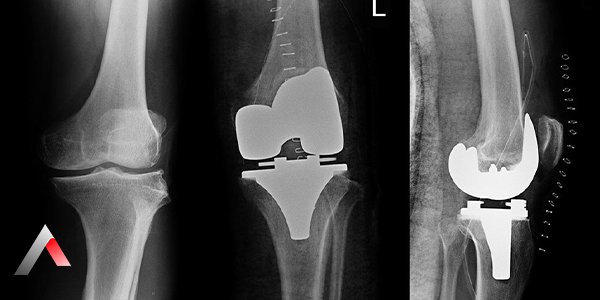

At A Life Health Group, we aim to provide the highest quality healthcare to patients of all ages. Total knee replacement surgery is performed to relieve pain, swelling, and limited mobility caused by cartilage wear, inflammation, or damage in the knee joint. The procedure involves replacing the damaged knee joint with an artificial implant. This approach offers an effective solution to reduce pain, improve mobility, and enhance overall quality of life.

Total knee replacement surgery involves replacing the entire surface of the knee joint with an artificial implant. The artificial joint is made of metal, ceramic, or specialized medical-grade plastics, designed to restore the natural movement and stability of the knee. The prosthesis supports both flexion and extension movements of the knee while reestablishing its load-bearing capacity.

Total_Knee_Replacement_Surgery_ec72679c.webp